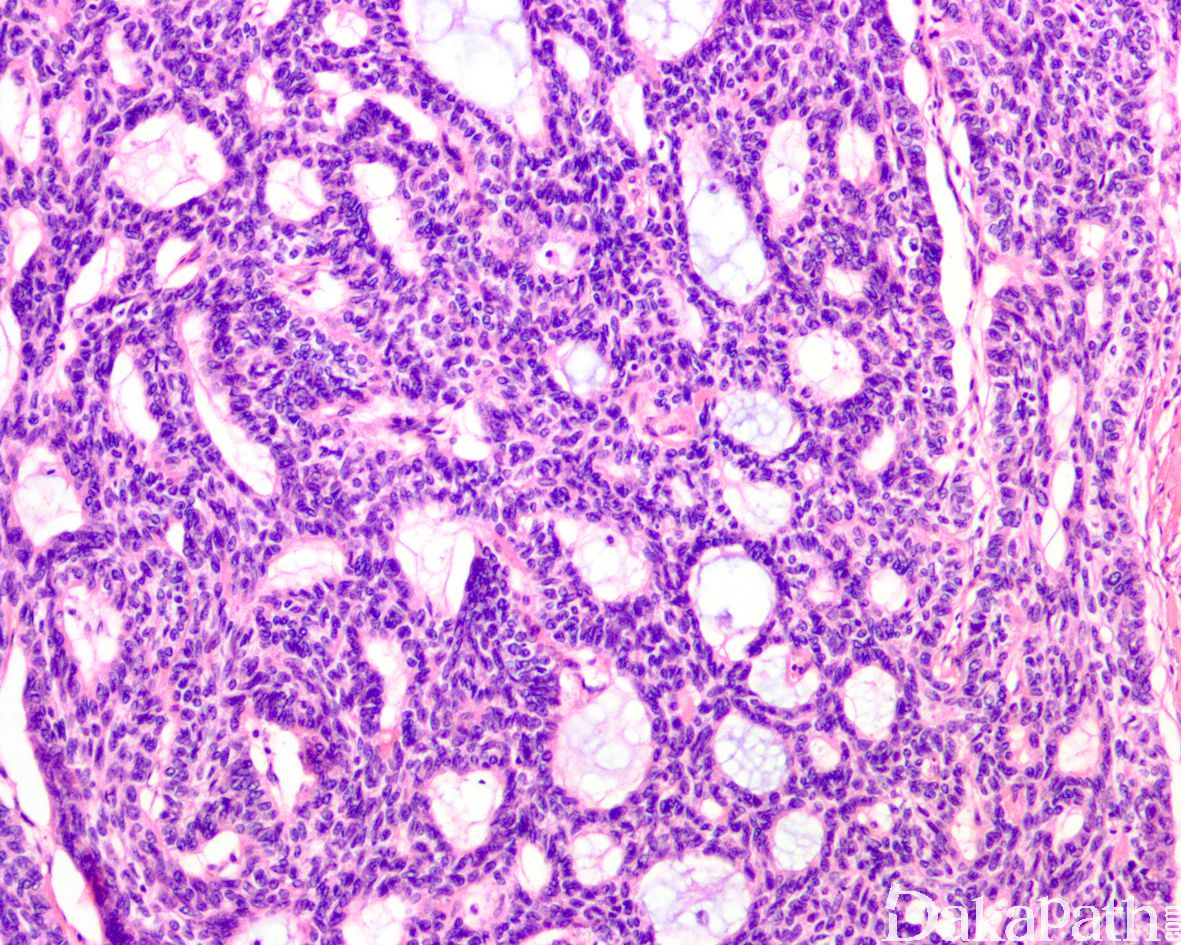

大多数病例显示多少不等的腺样囊性或筛状结构伴浓缩的分泌物及基底样小巢状结构;

部分病例形态与皮肤的基底细胞癌相似,可见大的基底细胞样细胞巢,周围呈栅状排列,并伴有中央坏死;

其它结构包括相互吻合的基底细胞巢、索,中央排列嗜酸性细胞的管状结构、大小不一、形态不规则的基底细胞巢等;

瘤细胞基底样,常见核沟;核分裂象多少不等(0-60 个/10HPF);